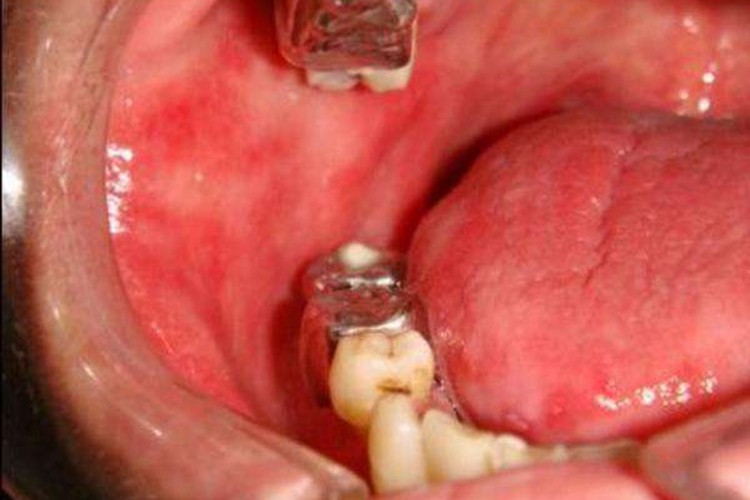

慢性红斑型(萎缩型)念珠菌病损害部位常在上颌义齿腭侧面接触的腭、龈黏膜,女性患者多见。黏膜呈亮红色水肿,或有黄白色的条索状或斑点状假膜。